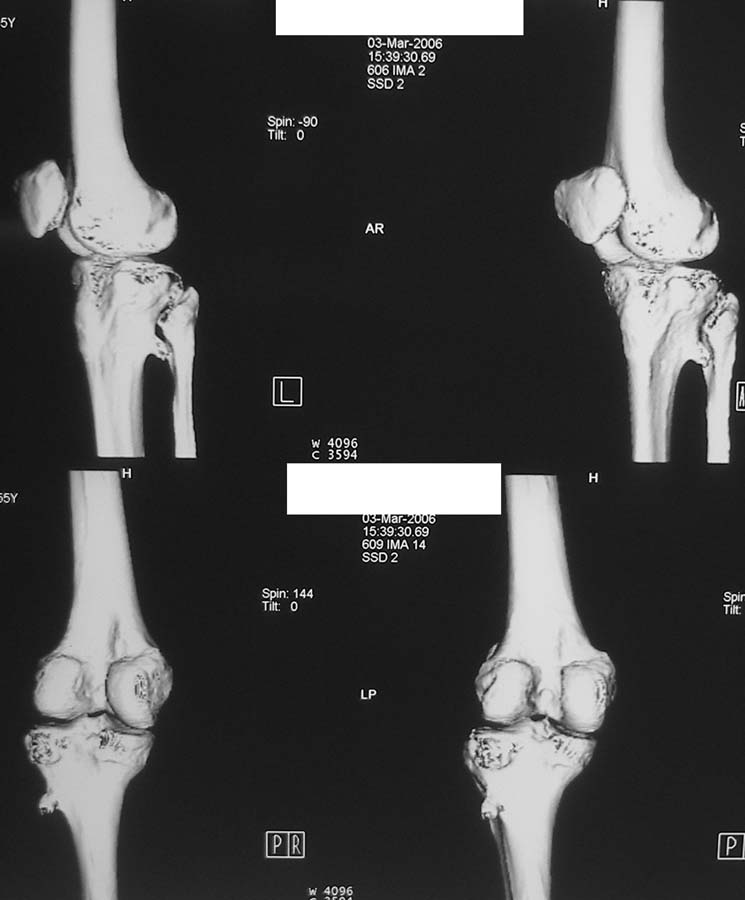

Женщина, 55 лет. С 2002 года - гонартроз. В настоящее время - боли в коленном суставе, стартовые боли, иногда в ночное время (проходит <от перемены положения ноги>).

Принимает НПВС, артрон-комплекс, внутрисуставно гиалган. Ревмопробы отрицательные. На рентгенограмме отметили сужение шейки малоберцовой кости, на спиральной КТ - экзостоз? Ваше мнение о целесообразности операции (велика вероятность повреждения нервов), предварительной биопсии?Спасибо! С уважением, А.В.Владзимирский Донецкий НИИ травматологии и ортопедии Донецк, Украина

Если боли связаны с гонартрозом, то показано тотальное эндопротезирование коленного сустава. Тип эндопротеза - мыщелковый, с сохранением задней крестовидной связки, сейчас таких моделей много (LCS, Balansis, Genesis, Scorpio, КЭКС-01 и другие, всё зависит с какими фирмами Вы работаете). Вопрос об удалении остеохондромы спорный, с одной стороны маловероятно ожидать у женщины 55 лет быстрого перерождения во вторичную хондросаркому при такой рентгенологической картине. Можно спротезировать коленный сустав и проводить рентгенконтроль каждые 6-12 мес. С другой стороны, если спротезировать и оставить остеохондрому, а она начнёт интенсивно рости, то её последующее радикальное удаление может ослабить тибиальный компонент эндопротеза. Проявляя онкологическую настороженность, остеохондрому лучше удалить первым этапом, до эндопротезирования с интервалом между операциями 6 мес. Производить биопсию в данном случае однозначно не целесообразно, так как при перерождении остеохондромы во вторичную хондросаркому на начальных стадиях малигнизации трудно гистологически отличить "добро" от "зла", и в этих ситуациях приоритет отдаётся рентгенологическим признакам. Техника операций при подобной остеохондроме стандартная - краевая резекция. Опасность повреждения малоберцового нерва существует всегда, но она зависит от мастерства хирурга и наличия микрохирургической техники (микроскоп не обязателен :)).

Вокруг коленного сустава беcсимптомные экзостозы встречаются очень часто, но они больше с медиальной стороны бедра и большеберцовой кости, и они выявляются при случайных рентгенологических исследованиях. Если нет сиптомов давления на малоберцовой нерв, то нет смысла из трогать, удаляется тогда, когда идет рост, поэтому только

наблюдение.

Насчет протезирования коленного сустава - при таком сохранном суставе навряд ли можно согласиться и совершенно согласен с Яковом, что надо искать источника боли сканированием или магнеторезонансными исследованиями.

Действительно, надо бы определиться в причине болевого синдрома. Подобные остеомы, как правило, немые. Болевой синдром может быть связан с околосуставнойт патолоией (например, поражение "гусиной лапки") или внутрисуставной. По R - граммам сустав очень даже сохранный (протезировать его явно нет необходимости), а отвергнуть внутрисуставную патологию или сразу ее максимально устранить поможет артроскопическое вмешательство. Повреждения менисков частенько симулируют остеоартроз.

Суставная щель на вид очень даже приличная. Мне кажется у больной есть варусная деформация колена, и возмможно с этим связано дегенаративное поражение медиального мениска и вся клиническая картина. Если это так, то эндопртезирование это слишком! Может что полегче: артроскопия и медиальная плюс-остеотомия.

Экзостоз скорее всего случайная находка, но динамического наблюдения безусловно требует.